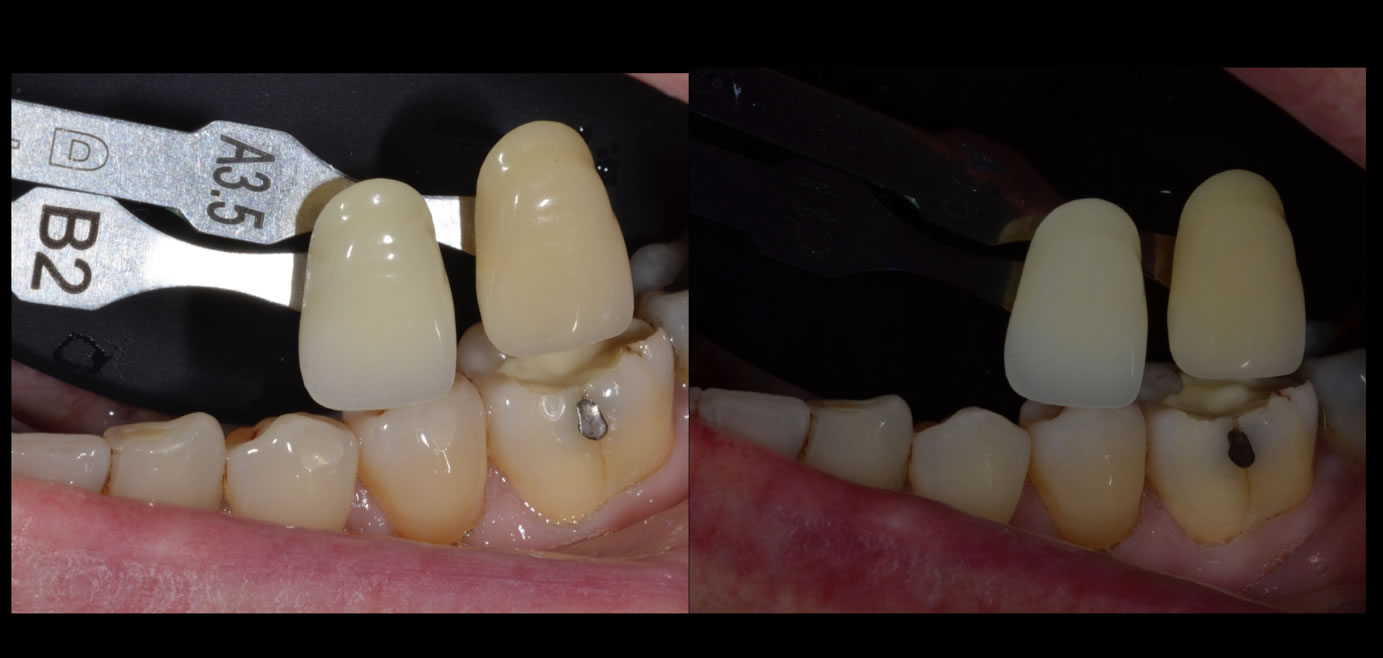

Cas clinique N°2 onlay Emax sur 36 :